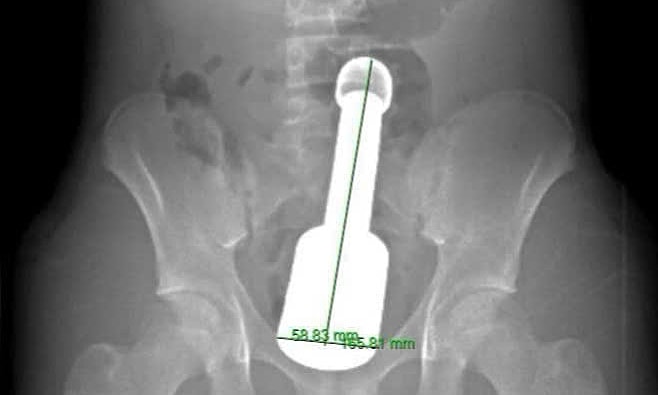

Bác sĩ Bệnh viện Hà Đông vừa gắp thành công chiếc chày dài 18 cm, đường kính 6 cm từ trực tràng một nam sinh 15 tuổi, giúp bệnh nhân tránh một cuộc mổ phanh ổ bụng.

Hình ảnh chụp chiếu phát hiện dị vật trong trực tràng. Ảnh: Bệnh viện cung cấp

Trước đó, nam sinh nhập viện cấp cứu trong tình trạng đau dữ dội vùng hạ vị. Bác sĩ thăm khám, phát hiện một dị vật lớn đã trôi sâu vào trực tràng, chèn ép các cơ quan vùng chậu. Hiện chưa rõ lý do và bối cảnh nam sinh hành động như trên.

Thử thách lớn nhất đối với ê kíp phẫu thuật là chiếc chày quá to so với giới hạn cực đại của cơ thắt hậu môn ở độ tuổi thiếu niên. Kích thước lớn cùng khối lượng nặng tạo ra "hiệu ứng chân không", khiến thành ruột hút chặt lấy bề mặt dị vật. Nếu bác sĩ chỉ dùng lực kéo thuần túy, nguy cơ rách tầng sinh môn hoặc vỡ trực tràng rất cao.